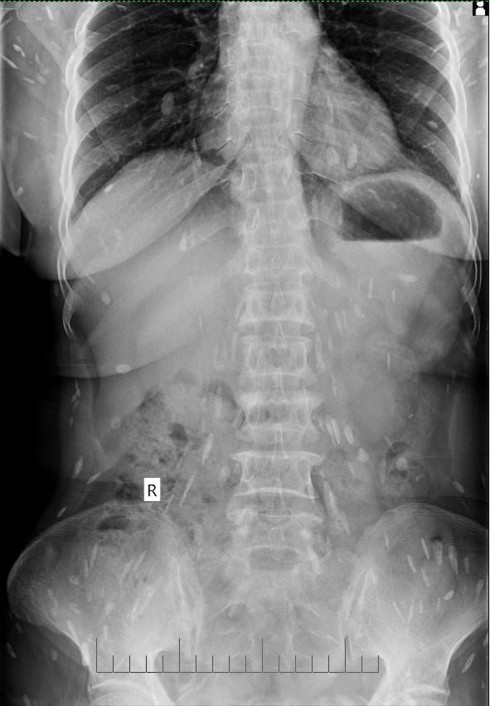

Bệnh viện Quốc tế Vinh (Nghệ An) vừa phát hiện một trường hợp nhiễm sán lá gan lớn. Bệnh nhân là bà P.T.Đ (55 tuổi, trú huyện Anh Sơn, Nghệ An). Thời gian qua, bà Đ. thường xuyên bị mệt mỏi, đầy bụng, đau đầu, đau ở vùng ngực và thắt lưng nên mua thuốc về tự điều trị. Tuy nhiên dấu hiệu bệnh không hề thuyên giảm.

Ngày 19/3, gia đình đưa bà đến bệnh viện để khám. Qua thăm khám, xét nghiệm, siêu âm, chụp X-quang, các bác sĩ kết luận bệnh nhân bị mắc bệnh sán lá gan sinh sống trong cơ thể đã nhiều năm, đang sinh sôi, lan ra trong nhiều bộ phận cơ thể. Người bệnh được kê thuốc và hướng dẫn lên bệnh viện tuyến trên để theo dõi, điều trị tiếp.